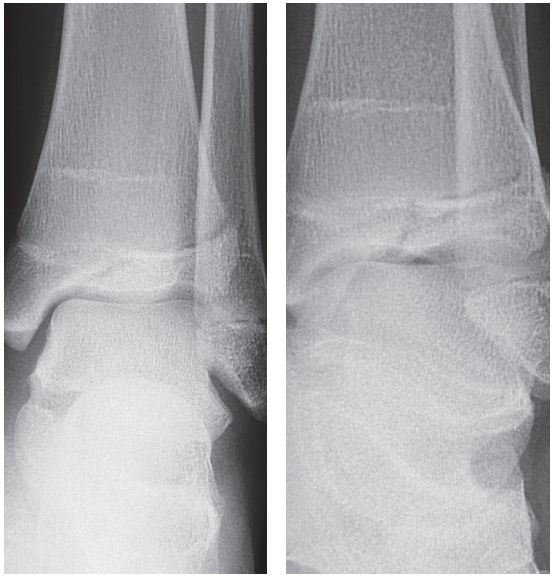

A 12-year-old female comes to your office complaining of left ankle pain. Her mother states that she was at the playground when she jumped down from the high bars and has been in pain ever since.